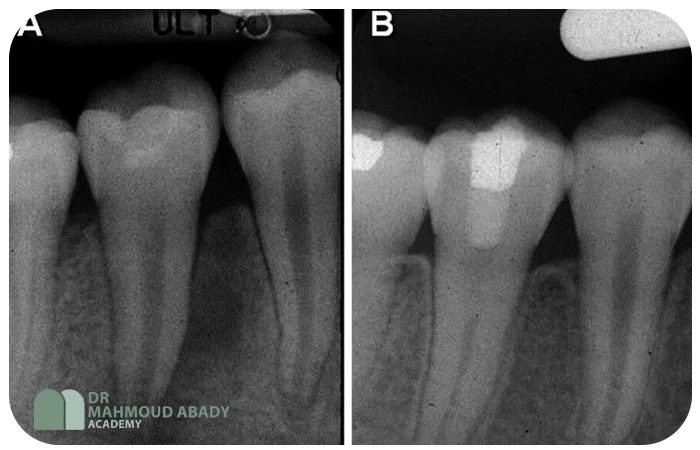

- پیگیری (Follow-up): پیگیریهای رادیوگرافیک و کلینیکی منظم (مثلاً هر 3-6 ماه) برای ارزیابی ادامه تکامل ریشه، بررسی علائم حیاتی پالپ و سلامت بافتهای پریاپیکال ضروری است.

- تعویض هیدروکسید کلسیم هر 3-6 ماه تا زمان تشکیل سد اپیکالی در رادیوگرافی (ممکن است 6 تا 24 ماه طول بکشد).

- تأیید محل صحیح پلاگ با رادیوگرافی.

- مزایا: کاهش قابل توجه طول درمان (معمولاً 1-2 جلسه)، ایجاد سد با کیفیت و سیلکنندگی بهتر، کاهش ریسک شکستگی دندان در طول درمان [4, 5].